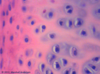

4

Q

A

Transitional epithelium